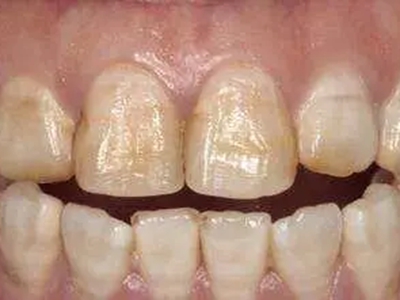

牙齿

小坑 · 缺损

牙釉质发育不全牙齿缺损有小坑图

重度牙釉质发育不全导致牙釉质表面呈棕褐色、棕黄色,其上有条状、窝状凹陷,并出现牙齿缺损,导致咬合关系破坏,也会出现对刺激敏感、疼痛等自觉症状。